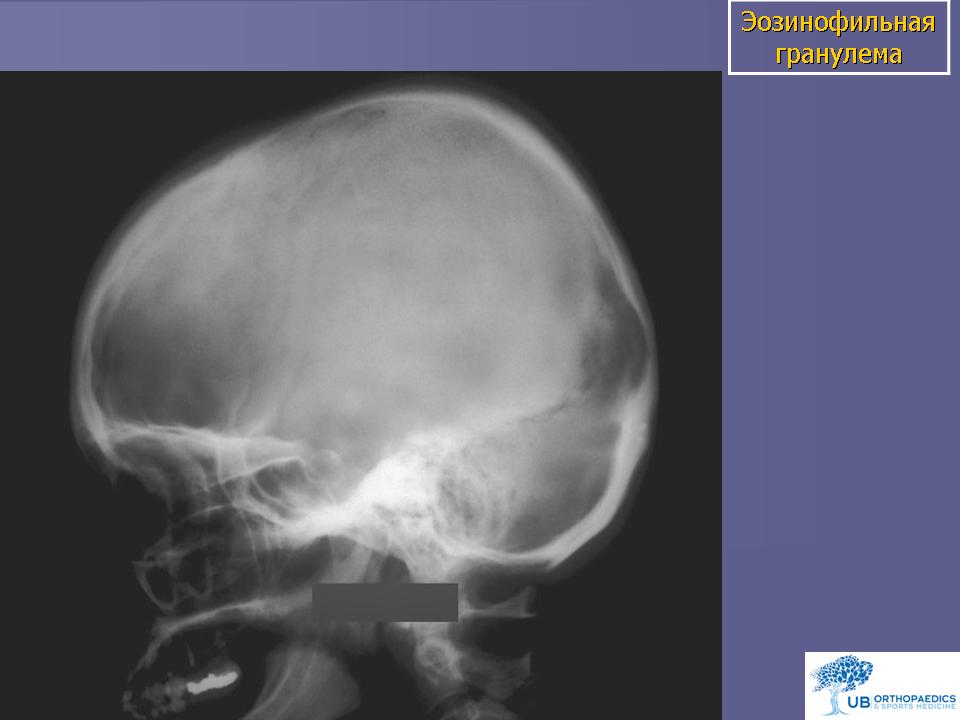

Эозинофильная гранулема. Это доброкачественное образование в кости, состоящее из гистиоцитов и эозинофилов, возникает в виде солитарной или множественной форм. В классическом варианте типичными для опухоли клетками являются гистиоциты, содержащие гранулы Лангерганса. Эозинофильная гранулема чаще поражает детей, реже встречается у лиц в возрасте старше 30 лет. Мультифокальный вариант отмечается у детей младшего возраста и может прогрессировать, что требует наравне с местным и системного лечения. Солитарные узлы всегда носят доброкачественный характер, заболевание не прогрессирует и имеет благоприятный прогноз. Клинически эозинофильная гранулема проявляется болью и ощущением дискомфорта в зоне поражения. Часто пальпаторно могут определяться мягкотканные массы. Рентгенологическая картина представлена в виде «выбитого» очага. Эозинофильная гранулема может поражать любую кость, однако чаще всего она встречается в костях черепа, в частности в челюсти, а также в костях таза, позвонках, других плоских костях. Опухоль может быстро расти, и рентгенологические признаки ее приобретают деструктивный характер. Больные с подозрением на эозинофильную гранулему должны тщательно обследоваться с использованием остеосцинтиграфии, обзорной рентгенографии костей скелета для исключения множественного поражения и в обязательном порядке - биопсии.

Эозинофильная гранулёма костей черепа